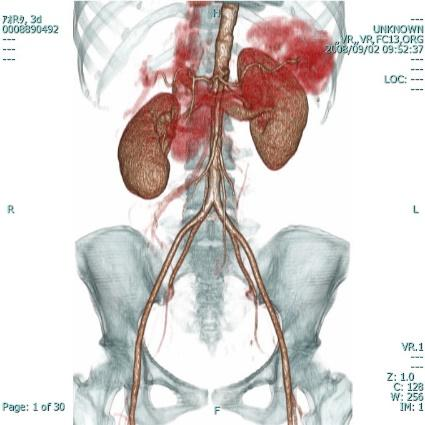

マルチスライスCT撮影装置

Supria

当院では64列マルチスライスCTを導入しています。

高速スキャンが可能で、一回の息止めで広範囲の撮影が可能です。

画像処理ソフトも使用し、

鮮明な3D画像や様々な角度からの断層画像を診断に役立てています。

また患者様の体に応じて、管電流を自動調整することにより、被ばく線量を抑えることが可能です。